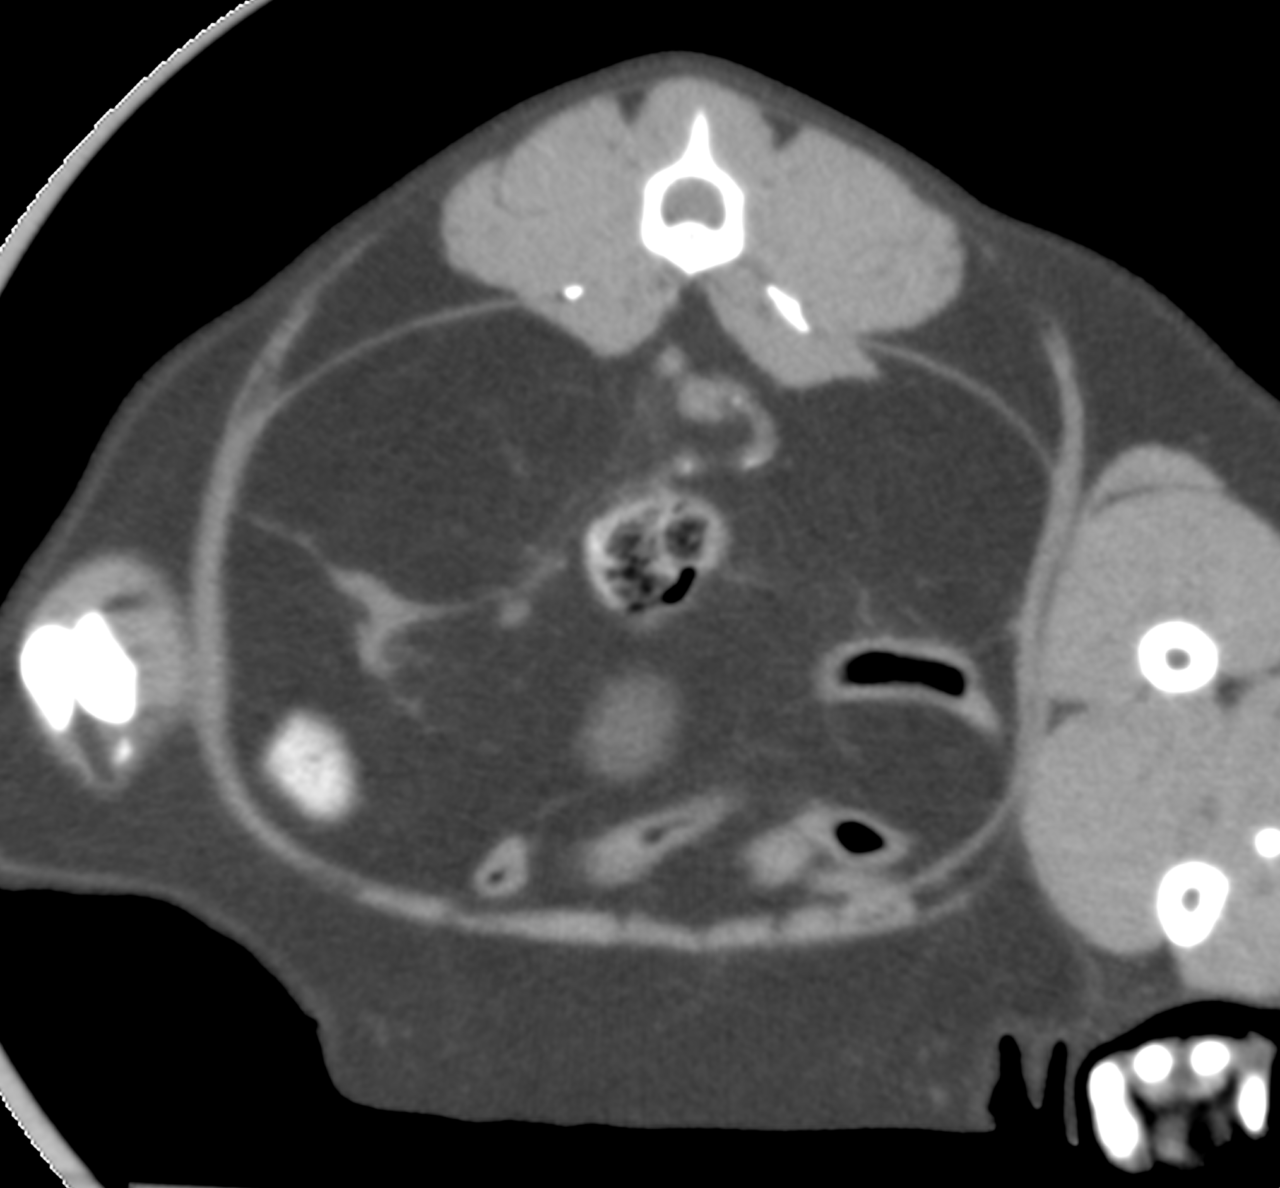

10歳の猫ちゃんの尿管閉塞を外科的に対応して欲しいと、主治医のリクエストがあり対応しました。無麻酔CTで結石の位置、大きさ、左右、個数など詳細を確認しました。右の腎盂拡張、尿管拡張、尿管結石が確認されました。顕微鏡下で右の腎盂〜尿管〜膀胱内に尿管ステントを留置しました。尿管結石の影響で広範囲に尿管の上皮に炎症が起こっています。その結果、尿管壁に線維化、狭窄、そして尿管の蠕動運動の機能低下などが起こります。ステントを入れて尿路を確保したので徐々に腎数値も改善してくるでしょう。また術後にはプレドニゾロンを使って尿管の炎症を抑えることも有効です。